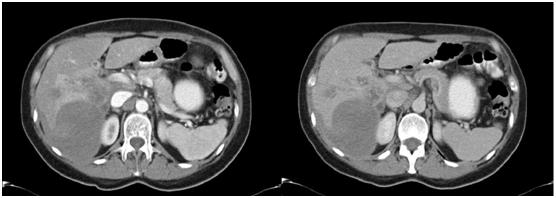

Figure 2 Abdominal MRI with contrast showing the presence in the liver of badly defined images with irregular borders, with hypointense centre and periferic enhancement after the application of the contrast in segments VI, VII and VIII suggesting micro abscesses.

In our patients, each one has a different image as a result of the varying diagnostic approach (abdominal ultrasound, CT scan or MRI scan). The patient in Case no.1 had two imaging examinations: abdominal ultrasound and CT scan. The abdominal ultrasound indicated the presence of a hyperechogenic area in right hepatic lobule (RHL) that compromised segments VI and VII. The CT scan showed the presence of a hipodense image of well defined borders at the level of segments VI and VII (see Fig. 1) that could correspond to a hepatic abscess. The patient in Case no. 2 had three imaging examinations: abdominal ultrasound, CT scan and MRI scan. The abdominal ultrasound showed the presence of hepatic nodules in segments VI and VII. The abdominal CT scan reported hipodense nodules in segments VI, VII and VIII with contrast medium enhancement at later stages, as well as hepatomegaly. The MRI scan demonstrated images suggestive of hepatic micro abscesses (Figure 2). The patient in Case no. 3 had two imaging examinations: abdominal ultrasound and abdominal CT scan. The abdominal ultrasound revealed hepatomegaly and fusiform and ovoid images on the left hepatic lobule (LHL) and dilatation of the biliary duct. The abdominal CT scan demonstrated multiple hipodense, heterogeneous images, with a diffuse distribution (Figure 3). Analyzing the findings of the imaging examinations of our three patients, despite the multiple formats of presentation, there is agreement of the majority of the findings with those reported by others elsewhere, although the imaging examinations did not permit us to make a definitive diagnosis in a nosological entity sense, in a certain manner the imaging examinations in conjunction with the clinical pictures and the blood analysis permitted us to put aside the possibilities of other etiologies, particularly neoplastic or infectious (hepatic abscesses and other parasitosis, such as hydatidosis).